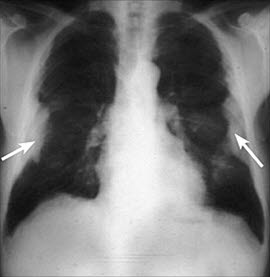

Pleurale plakkPleuraplakk er fortykkelser i lungehinnen (pleura) som omhyller lungene. Påvisning av pleuraplakk forteller at vedkommende person har vært utsatt for, eksponert for, asbest, for eksempel i yrket sitt. Pleuraplakk er den vanligste reaksjonen fra lungene på tidligere asbestinhalasjon. De fleste plakk gir ikke opphav til symptomer, og det er ikke holdepunkter for at plakk omdannes til kreftsykdom. Tilstanden er en utelukkelsesdiagnose. Det betyr at det må gjennomføres en utredning for å utelukke andre underliggende sykdommer.

Tilstanden er som sagt forårsaket av eksponering for asbest. Pleuralplakk representerer avsettinger av kollagenfibre på den ytre lungehinnen. Med tiden kan denne fortykkelsen forkalkes og bli synlig på røntgen. Pleuraplakk er det tidligste funnet som kan opptre som tegn på asbesteksponering. De kommer gjerne til syne 10-20 år etter eksponeringen. Det antas at plakk-utviklingen skyldes irritasjon fra fibrene mot lungehinnen. Når disse plakkene følges over tid, vil man observere at de vokser og minker. Plakk finnes først og fremst mellom 6. og 9. ribben og langs mellomgulvet (diafragma).

Forkalkninger (kalsifikasjoner) i plakk oppdages ved lungerøntgen hos 20 prosent, ved høyoppløselig CT hos 50 prosent og ved mikroskopisk undersøkelse av vevsprøve (biopsi) hos 80 prosent. Ethvert nytt pleuraplakk som oppstår, krever en grundig utredning, inklusive tuberkulose-testing og vevsprøve. En vevsprøve innebærer at en tynn nål stikkes gjennom brystveggen og inn i den fortykkede lungehinnen.